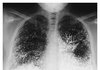

수은먹고 자살 시도한 여자의 엑스레이